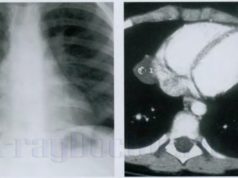

Рентгенологическое исследование грудной клетки и сердца

Лучевое исследование грудной клетки подразумевает диагностику патологий костных структур: позвоночника, грудины, ребер, а также легких, области средостения и плевральной полости....